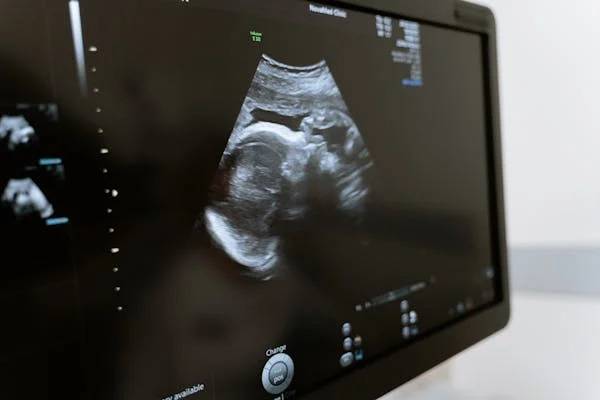

현재는 비침습적 산전 DNA 검사 (Non-Invasive Prenatal Paternity, NIPP) 기술이 발달해

산모의 혈액만으로도 태아의 유전자를 추출해 분석할 수 있게 되었습니다.

산모의 혈액 속 ‘태반 유래 DNA’를 통해 태아의 유전정보 확보

임신 7~10주 이후 가능

남성의 DNA 샘플과 비교하여 99.9% 이상의 정확도

안전성 100%, 유산 위험 없음